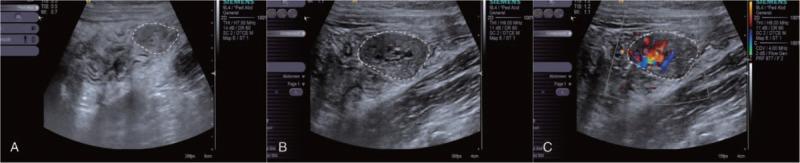

This study was established to evaluate the diagnostic value of ultrasonography in screening colorectal polyps in children and to discuss the necessity of colonic preparation before an ultrasonic examination.In this study, 288 children with colorectal polyps managed at our hospital between January 2007 and December 2016 were retrospectively reviewed. All patients were examined before and after basic colon preparation. The colorectal polyps were confirmed by colonoscopy/laparotomy and histopathology. Among all 288 patients, solitary polyps were identified in 278 patients (96.52%), and multiple polyps were identified in 10 patients (43 polyps) (3.48%) by colonoscopy/laparotomy and histopathology.By ultrasonic examination, 264 cases (264/278) were detected as solitary polyp and 9 cases (9/10) as multiple polyps (31 polyps). In 278 solitary polyps, 180 (64.74%) were detected by ultrasonic examination without a colon preparation. Following glycerine enema (10-20 mL) treatment, 264 (94.96%) cases were detected by ultrasonic examination. The sensitivity and specificity of ultrasonography with glycerine enema for the detection of colorectal polyps were 94.96% and 100%, respectively. Colon preparation significantly increased the proportion of polyps identified by ultrasonography (P < .0001), as well as the diagnostic rate of polyps in rectum, sigmoid colon and descending colon (P < .05).Ultrasonography can be the primary diagnostic method for screening colorectal polyps in children on the strength of its safety, validity, and accuracy. Basic colon preparation with glycerine enema is recommended for children, which enable the detection of intraluminal lesions before ultrasonic examination.

本研究旨在评估超声检查在儿童结直肠息肉筛查中的诊断价值,并探讨超声检查前进行肠道准备的必要性。本研究回顾性分析了2007年1月至2016年12月在我院接受治疗的288例结直肠息肉患儿。所有患者在进行基础肠道准备前后均接受检查。结直肠息肉通过结肠镜检查/剖腹手术及组织病理学确诊。在全部288例患者中,通过结肠镜检查/剖腹手术及组织病理学发现,278例患者(96.52%)为单发息肉,10例患者(43枚息肉)(3.48%)为多发息肉。通过超声检查,264例(264/278)被检测为单发息肉,9例(9/10)被检测为多发息肉(31枚息肉)。在278例单发息肉中,180例(64.74%)在未进行肠道准备的情况下通过超声检查被发现。经甘油灌肠(10 - 20毫升)治疗后,264例(94.96%)通过超声检查被发现。甘油灌肠后超声检查对结直肠息肉检测的敏感性和特异性分别为94.96%和100%。肠道准备显著提高了超声检查发现息肉的比例(P < 0.0001),以及直肠、乙状结肠和降结肠息肉的诊断率(P < 0.05)。基于其安全性、有效性和准确性,超声检查可作为儿童结直肠息肉筛查的主要诊断方法。建议对儿童采用甘油灌肠进行基础肠道准备,以便在超声检查前发现腔内病变。